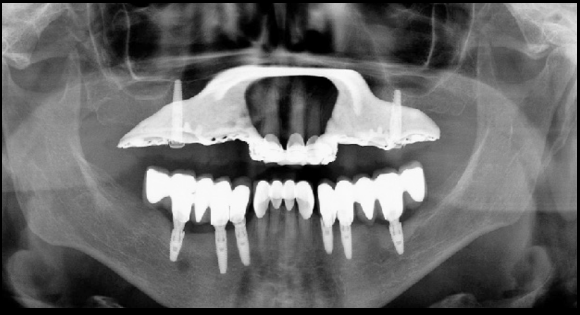

Errors in patient preparation

Image 1: Ghost image of a necklace/chain. Also jaw surgery.

Image 2: Lead apron